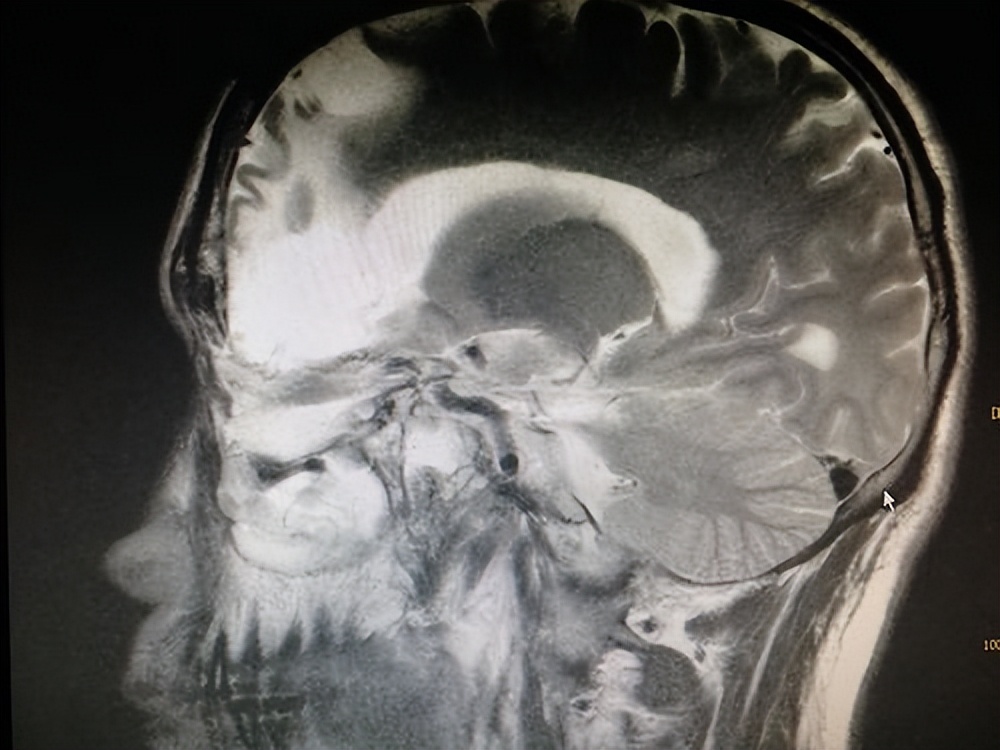

NIP多起源于鼻腔外侧壁(82%),好发部位依次为:上颌窦(53.9%)、筛窦(31.6%)、鼻中隔(9.9%)、额窦及蝶窦分别占6.5%和3.5%。手术切除目前是NIP最佳的治疗方式。为了达到更好的诊断效果,通常采用CT和MRI对内翻性乳头状瘤范围进行评估。CT影像技术能准确判断NIP侵犯范围及来源,为手术提供重要依据,多表现为密度均匀或不均匀的软组织团块影,软组织影内含低密度气泡影是NIP的特征性表现,因其有破坏性,易造成临近骨质破坏。NIP在MRI中多表现为高低信号相见的卷曲脑回状条纹影(图4A),术前CT和MRI联合检查可以更好的鉴别肿瘤范围及区分肿瘤是否伴有炎性阻塞、息肉及囊性变等情况。